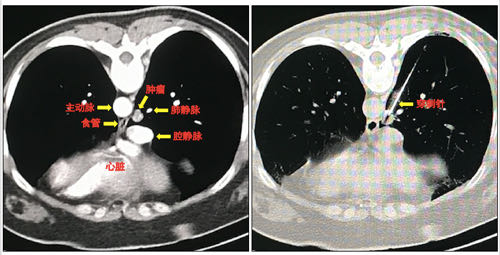

对于某些能在CT上看到的小结节,有的时候需要穿刺活检,明确它的病理性质,这样就可以增加诊断的正确率,对于指导治疗也非常有帮助。

但是人是一个活体,每个结节生长部位不同,穿刺难度也不同。比如肺里的结节还会随着呼吸和心跳产生移动。能看到的,未必能够穿到。

下面这张图,就是CT片子上显示的肺部结节。

这个结节位置很深,如果长在肺的边缘,很多医生都可以穿刺成功。

但是这个结节长在肺内非常深的位置,而且最难的是,它不仅会随着呼吸移动,它还紧邻主动脉。穿刺的时候,如果病人剧烈咳嗽,或者医生的手稍微一抖,那么你肯定知道结局。